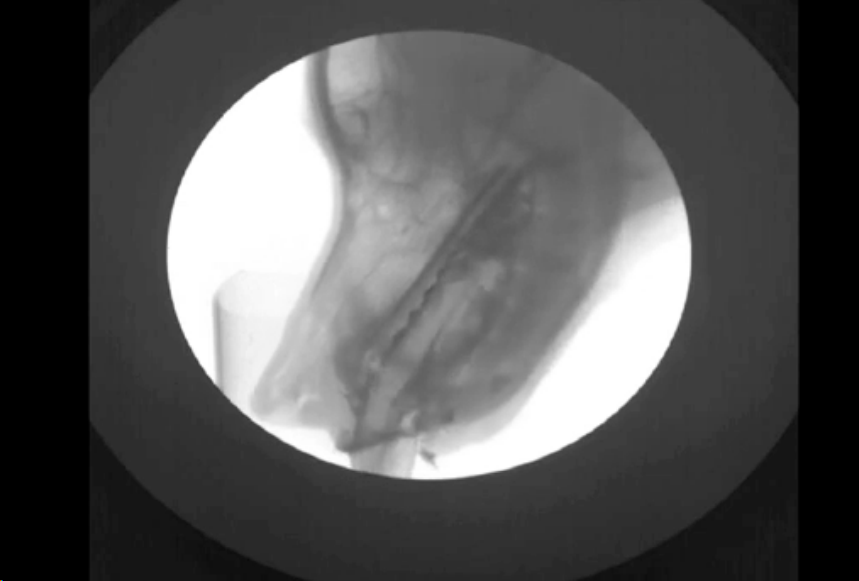

El revelado de la placa puede ser manual o automático con reveladora, para la visualización se usa un negatoscopio. Para intensificar la imagen se usan pantallas fluorescentes; esto reduce la dosis absorbida, pero reduce la resolución y aumenta el ruido. Sirve para estudios en movimiento, imágenes de menor tamaño e invertidas. Se usa sistema de telefisión.

Los arcos de fluoroscopia de componen de: